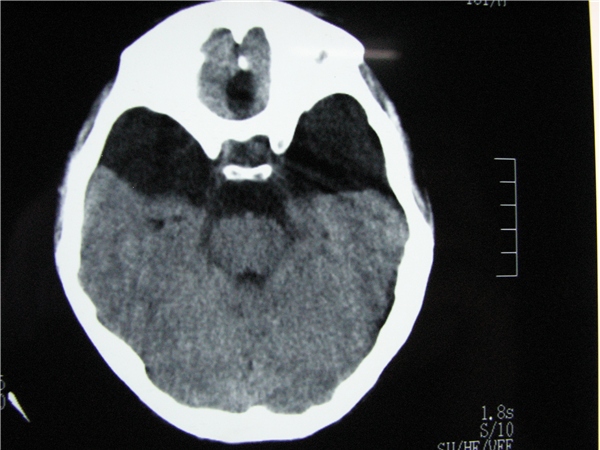

标题: CT20748:M 15Y 头痛,以前有外伤史请老师看看除了囊肿还有别 [打印本页]

标题: CT20748:M 15Y 头痛,以前有外伤史请老师看看除了囊肿还有别

m 15y 头痛,以前有外伤史请老师看看除了囊肿还有别的吗?

蛛网膜囊肿。眼拙,看不出别的,倒是看到了双侧大脑中动脉影,类似“致密动脉征”。

双侧侧裂池和纵裂池近前颅窝蛛网膜囊肿。

不能除外脑穿通畸形

无明显占位及负占位效应,考虑软化灶并脑室穿通畸形囊肿、局限性脑萎缩

蛛网膜囊肿,不能除外脑穿通畸形,支持。